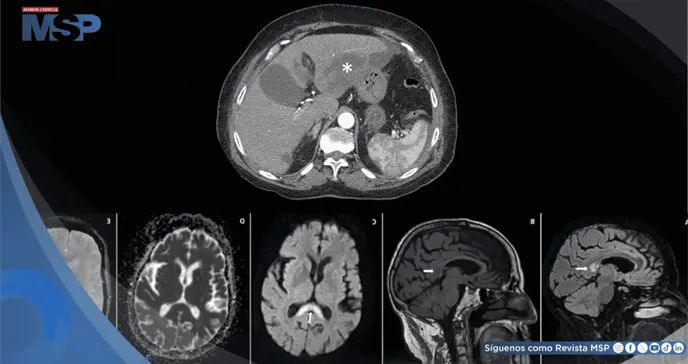

Una tomografía computarizada (TC) abdominal confirmó la gravedad del cuadro, identificando un absceso grande y multiloculado en el lóbulo izquierdo del hígado, de aproximadamente 7x7 cm, acompañado de líquido (ascitis) alrededor del hígado.